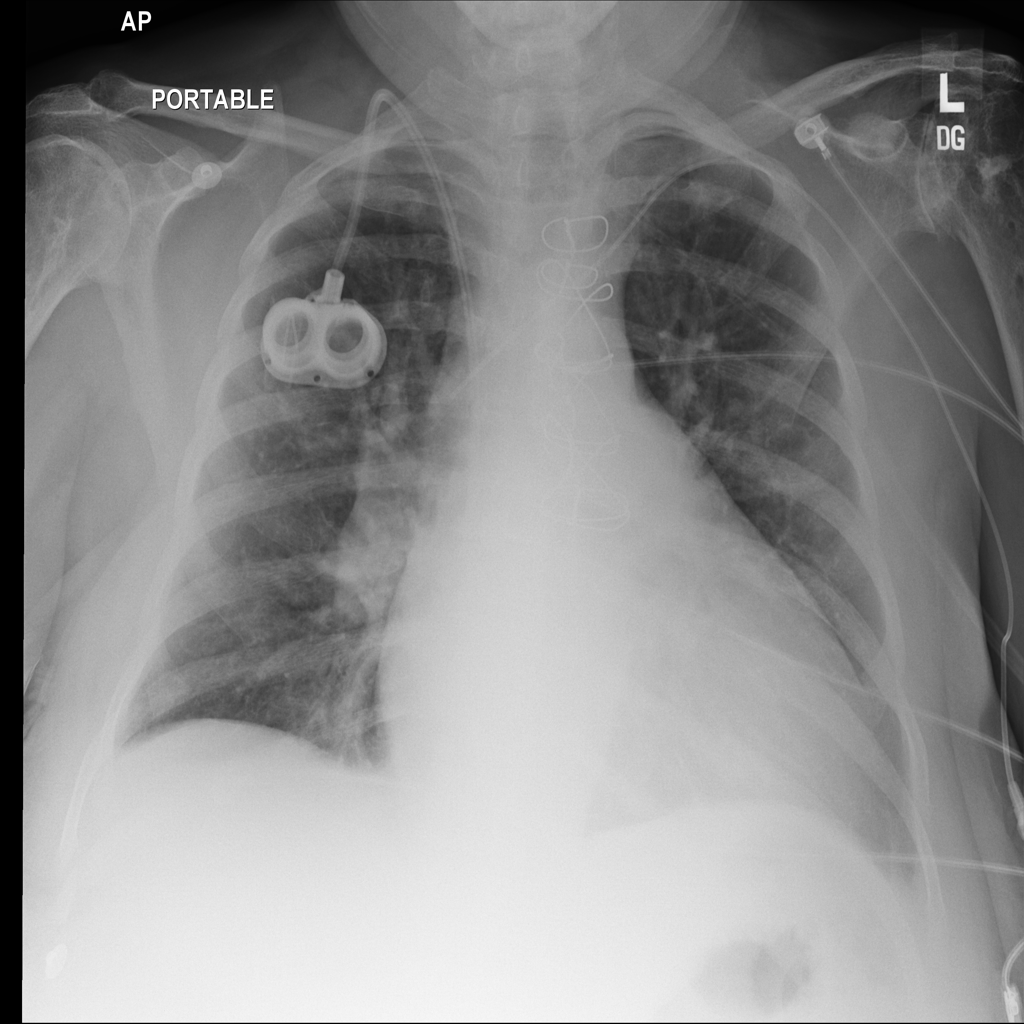

PAT-3384 · IMG-000Cardiomegaly

PAT-3384 · IMG-000

AP